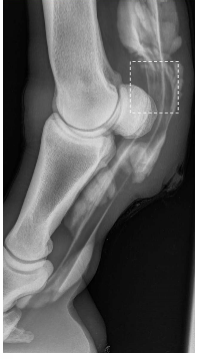

• what is your top differential?

digital flexor tendon sheath injury